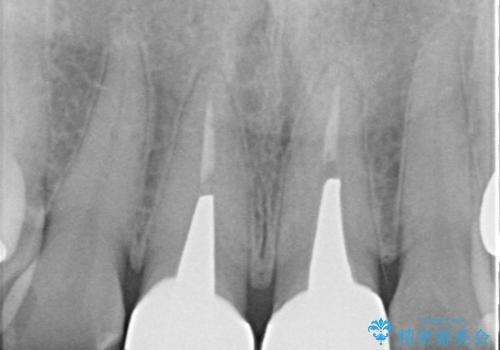

- 前歯の変色を主訴に来院されました。

根管治療、土台のやりかえも提案しましたが、金銭的理由より、クラウンのみの修復としています。

今後痛みが出た場合は、外科的歯内療法での対応を希望されています。